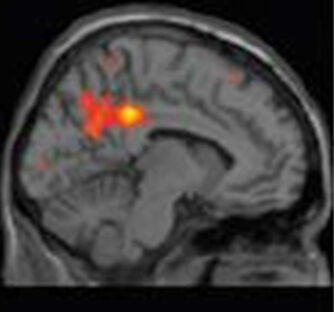

Evaluation of a gene therapy approach in a model of Parkinson’s disease